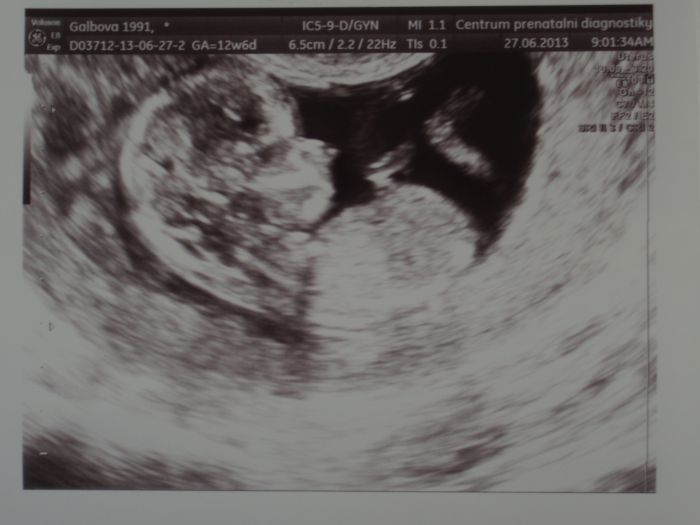

Holky tak pridavam fotecku naseho drobecka ze screeningu a prukazku